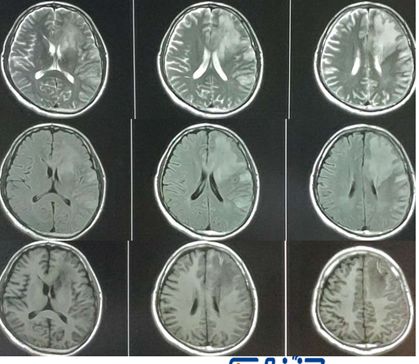

男, 41,头痛头晕3个月。

答案:结核性肉芽肿

又是非常丰富的影像学资料。乍一看又像是个大瘤子,鉴别脱髓鞘假瘤。

灌注成像,病灶这一块有高有低,像是病灶核心有点高灌注,水肿的地方低灌注。波谱也只能提示神经元受损,有一点脂质波,没有很强的特异性。DWI高,似乎支持淋巴瘤。没想到结果出来却是结核性肉芽肿。

复习一下脑结核性肉芽肿(也称结核瘤)的影像特点:

圆形或分叶样结节,CT呈等密度、稍高密度或混杂密度。核磁上T1等信号或低信号,T2新鲜病灶可呈稍高信号,老病灶常呈低信号。

中心干酪样坏死的信号变化取决于坏死物内水的含量及蛋白质、脂质浓度,可呈长T1、长 T2,等T1、长T2信号,等T1、短T2信号改变。

可有伴中至重度水肿。增强扫描可呈结节样或环形强化。CT上可表现为中心钙化、环以周围增强,称为靶征。

一般总感觉结核性肉芽肿似乎比较小,没想到也遇到这种长的比较大和其他肿瘤相似的。今后要注意鉴别。